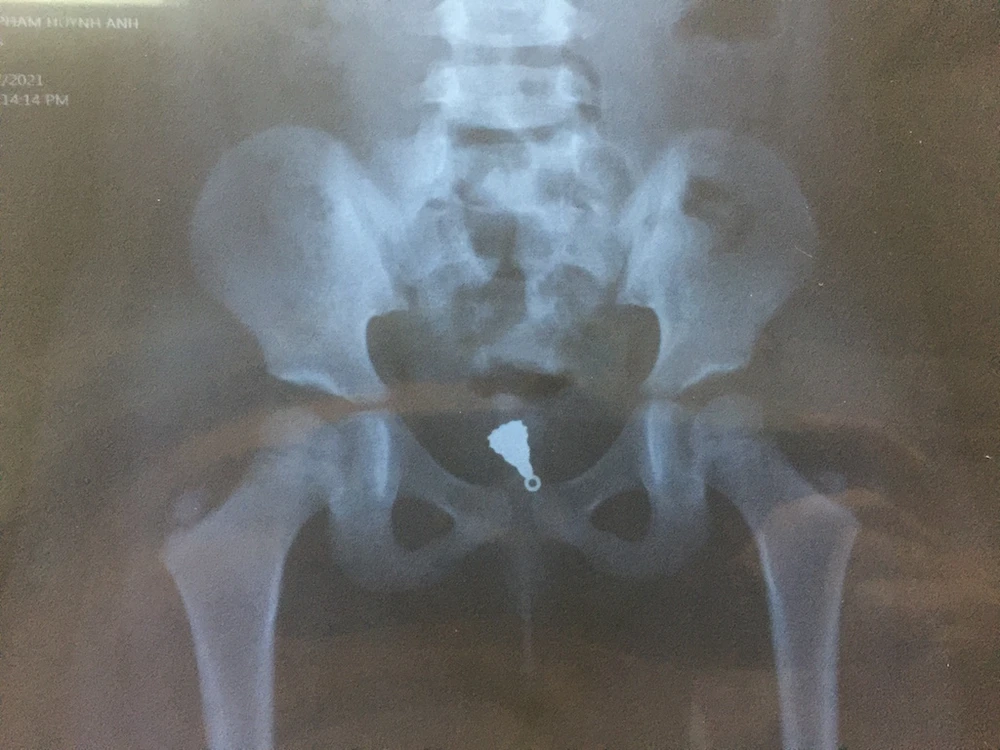

Phim X-quang thể hiện mặt dây chuyền nằm sâu trong âm đạo bé gái. Ảnh: BVCC

Kết quả chụp Xquang vùng bụng chậu cho thấy có dị vật cản quang vùng tiểu khung dạng mặt dây chuyền. Ngay lập tức bệnh nhi được chỉ định gây mê để lấy dị vật.